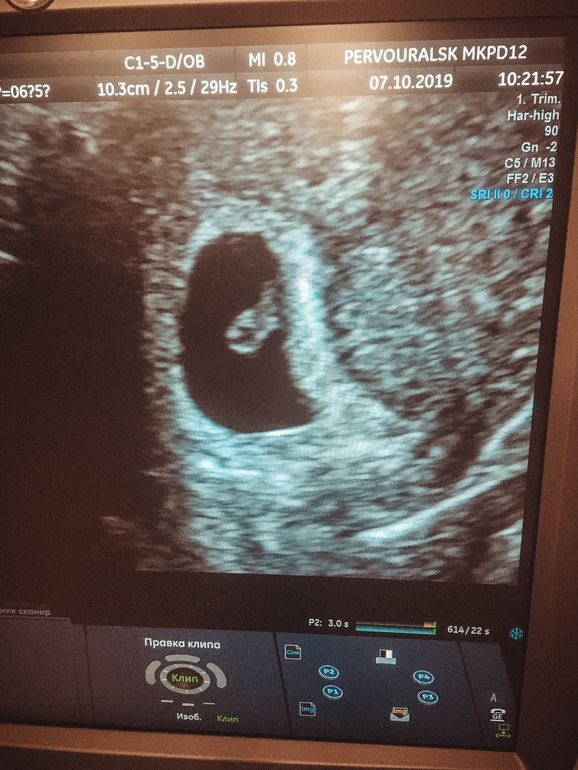

Знакомство с малышом🥰

Сходила на приём сегодня, поставили на учёт.

Вес меня не порадовал, хотя не чувствую я его на себе, мне кажется я стройнее. Думаю все же это мышцы, полгода силовых тренировок. Сделали узи, послушала сердечко 💖 🥰🥰🥰ощущения будто в первый раз.

Малыш размером 5,5 мм, сердцебиение 129.